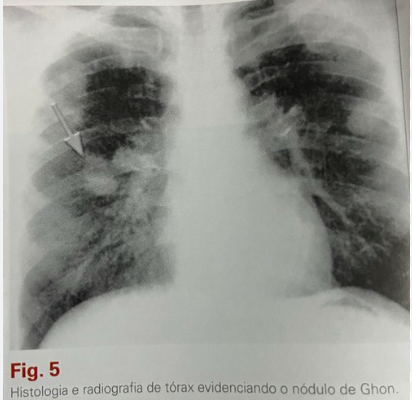

foco granulomatoso pulmonar de onde tudo começou é chamado de

nódulo de Ghon (nódulo primário)

nódulo de Ghon (características)

• geralmente único, se localizando no terço médio (lobo médio, língula, parte inferior do lobo superior ou parte superior do lobo inferior)

• foco pequeno, que pode evoluir para dimensões de > 8mm, aparecendo no raio-x como um nódulo solitário